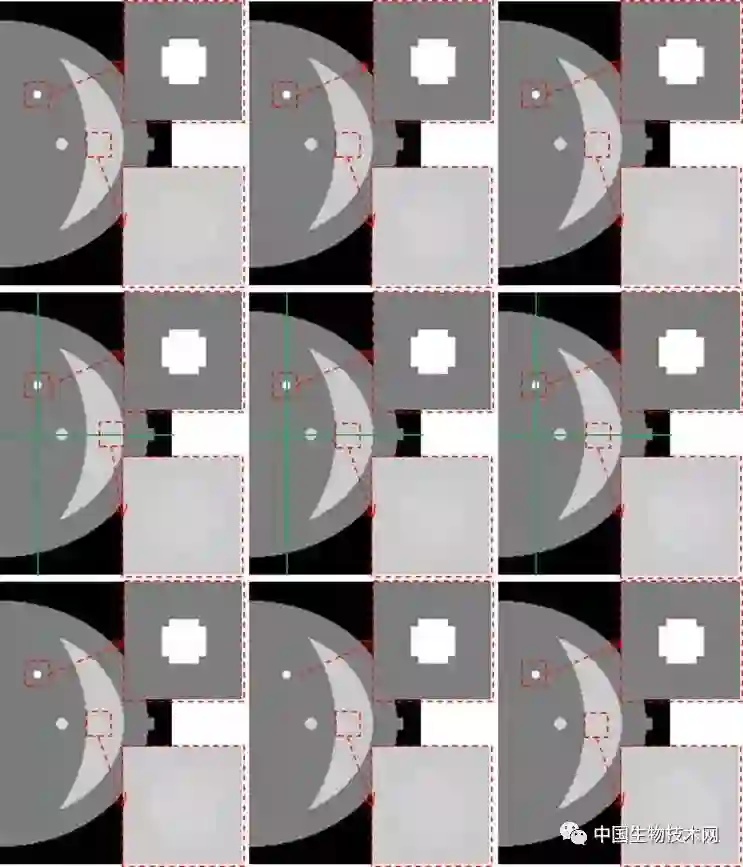

图2. 不同噪声水平下乳腺体模的重建结果。从上到下的行分别对应0.1%、0.5%和1%水平的高斯噪声,从左到右的列分别对应ASD-POCS、SD-SART和MTTV-POCS算法。